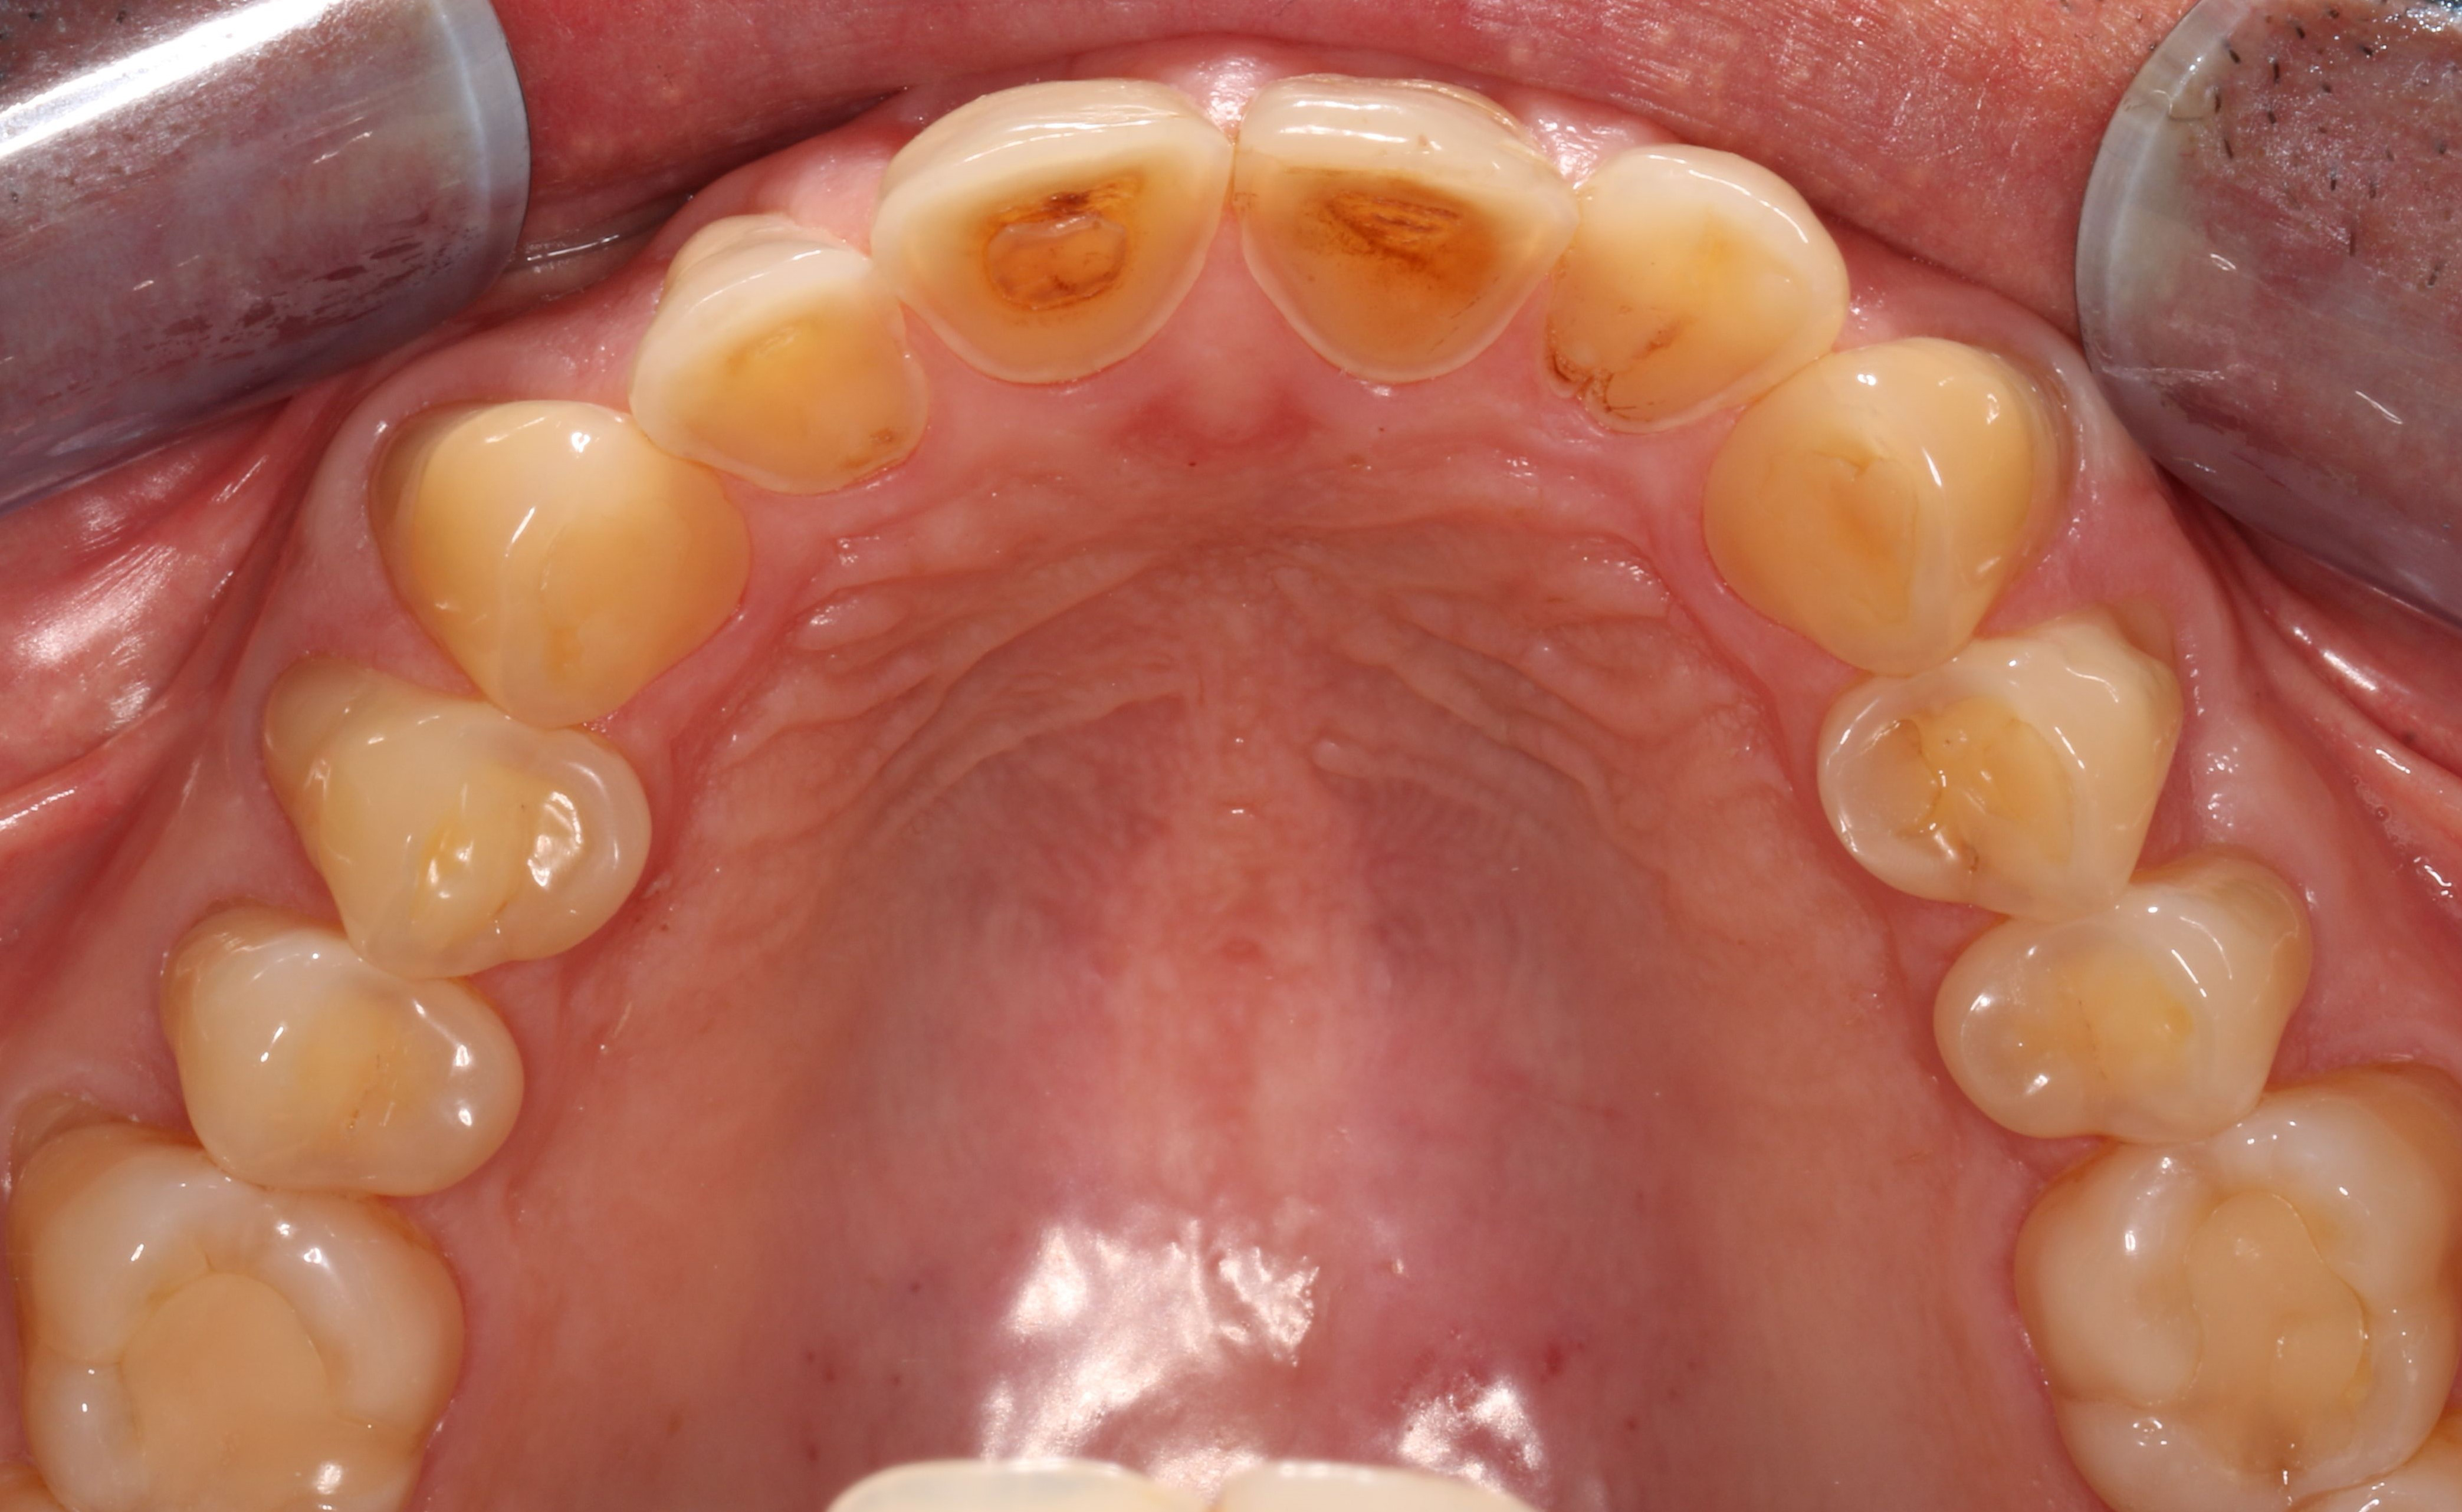

Die Ursachen für die Zahnerkrankung (Abb.1) sind vielfältig und gerade endogene Faktoren nicht einfach abzustellen. Es gibt jedoch Inhaltsstoffe, wie etwa Zinnsalze und Biopolymere, die vor Erosionen schützen und von Experten empfohlen werden.

Erosionsgebiss (© Schlüter/Medizinische

Hochschule Hannover)